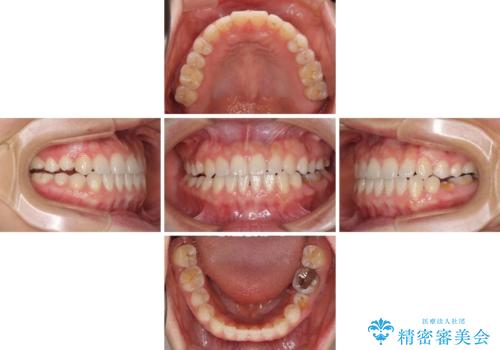

- 上下の前歯の隙間を気にして来院された患者様です。

インビザラインを用い、上下歯列のスペースを閉じていくこととしました。

治療期間中は奥歯がほとんど咬めない状態が続き、食事に大変苦労されました。

最終的には隙間もしっかりと閉じ、奥歯も咬みやすい状態でしあげることができました。